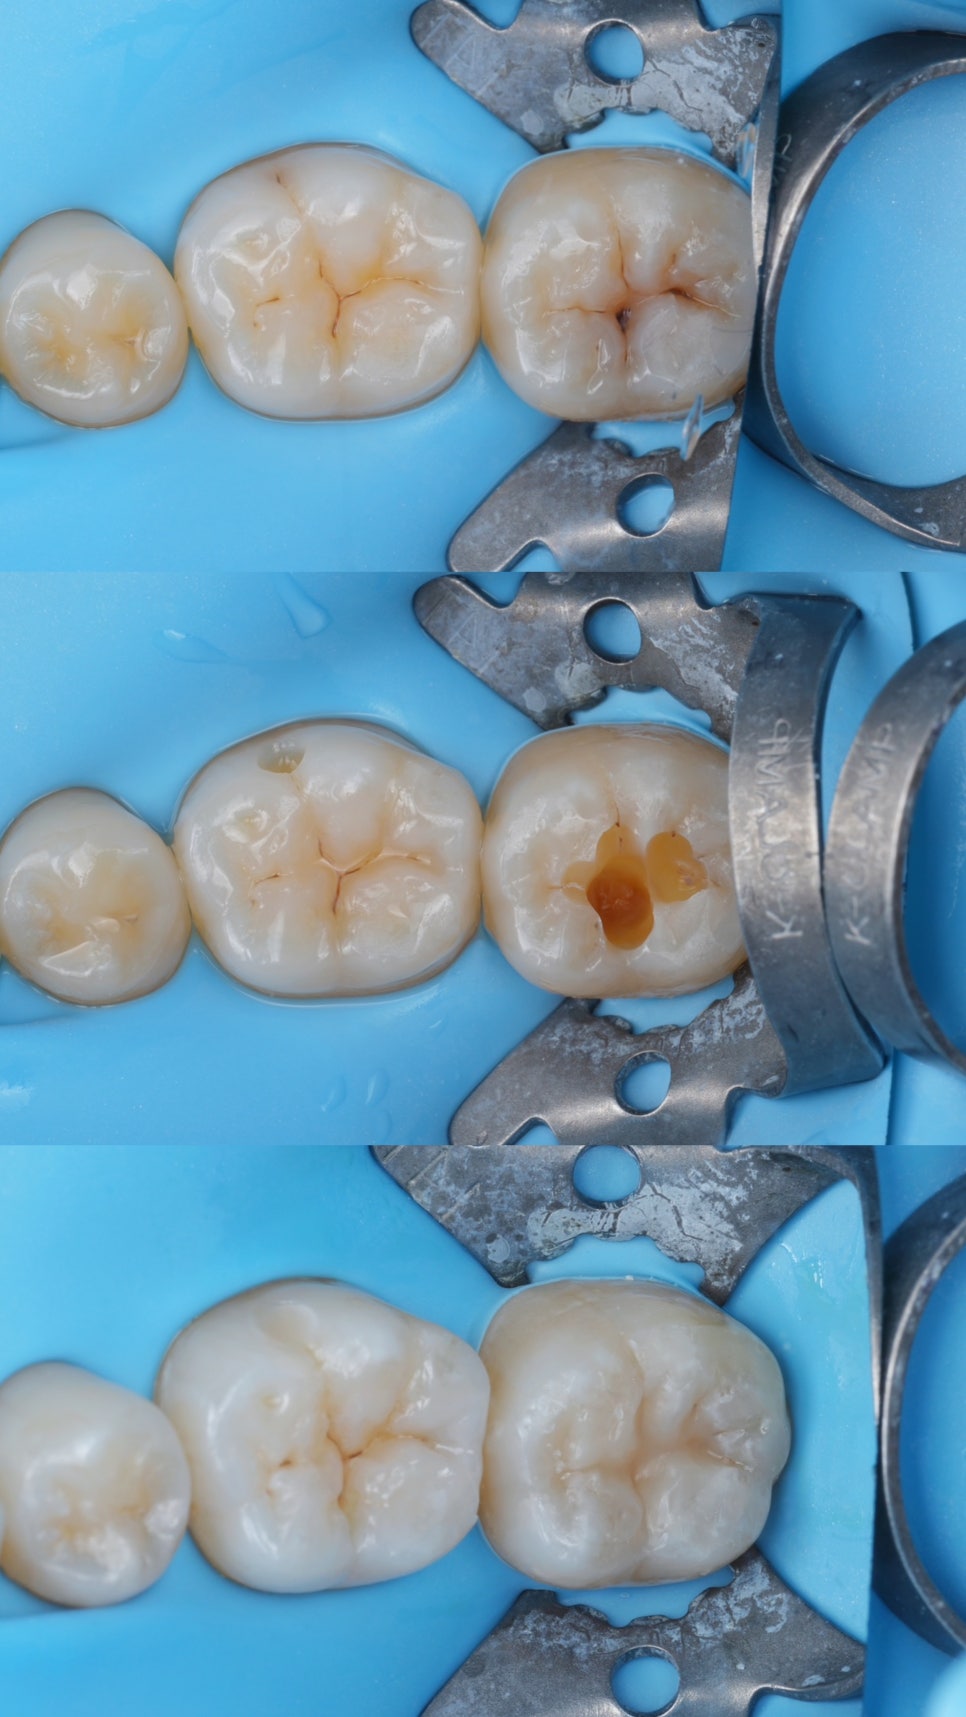

일단 우식을 삭제하기 전에 먼저

✦ 퀵스 플로우를 섬세하게

pit and fissure를 적셔줍니다.

필요하면 약하게 바람을 불어도 되는데

초짜때 바람불면 망할 가능성이 높아요.

그냥 살살 잘 흘려보내주시고,

✦ 마이크로 브러쉬를 살짝 얹고

퀵스를 좀 더 짜서 브러쉬를 덮어줍니다.

그리고 광중합을 한 뒤 떼어내면

교합면의 pit and fissure가

퀵스에 인상이 돼서 나오겠죠?

그걸 나중에 패커블레진에 찍어서

교두경사를 재현하는 테크닉이에요.

그러니까 패커블 레진을 일단

와동을 채울 정도로 잘 적용해놓고

✦ 그 위에 '테플론 테이프'를 덮은 다음

스탬프를 찍어야해요.

그리고 테이프를 살살 떼어낸 다음

✦ 피슈라를 이용해서

와동 바깥으로 밀려나온 레진을

떼어내준 다음에 광중합하세요.

그러면 어느정도 결과가 나옵니다 ㅎㅎ

이 과정에서 와동이나 와동에 올려놓은 레진 등

습기에 취약하기때문에

반드시 러버댐을 장착하시는 게 좋고요